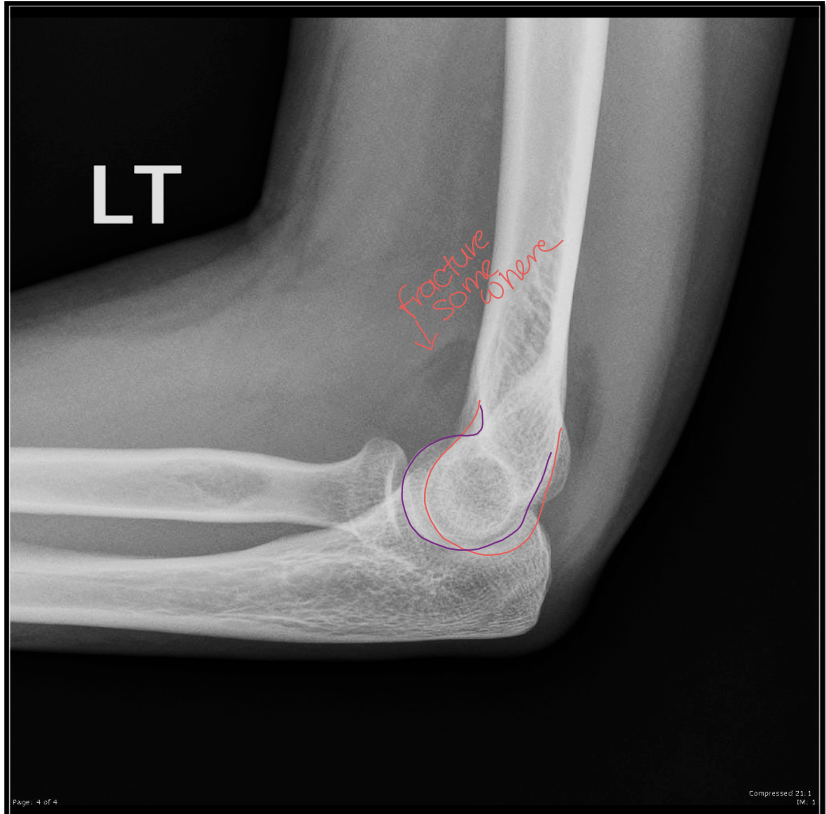

Lateral Elbow Criteria

A

• elbow flexed 90

• capitulum and trochlea superimposed

• articulating surfaces of the radial head and coronoid process are aligned

Q

What is the positioning fault?

How would you fix it?

• hand is too low

• lateral condyle more distal

• need to raise hand